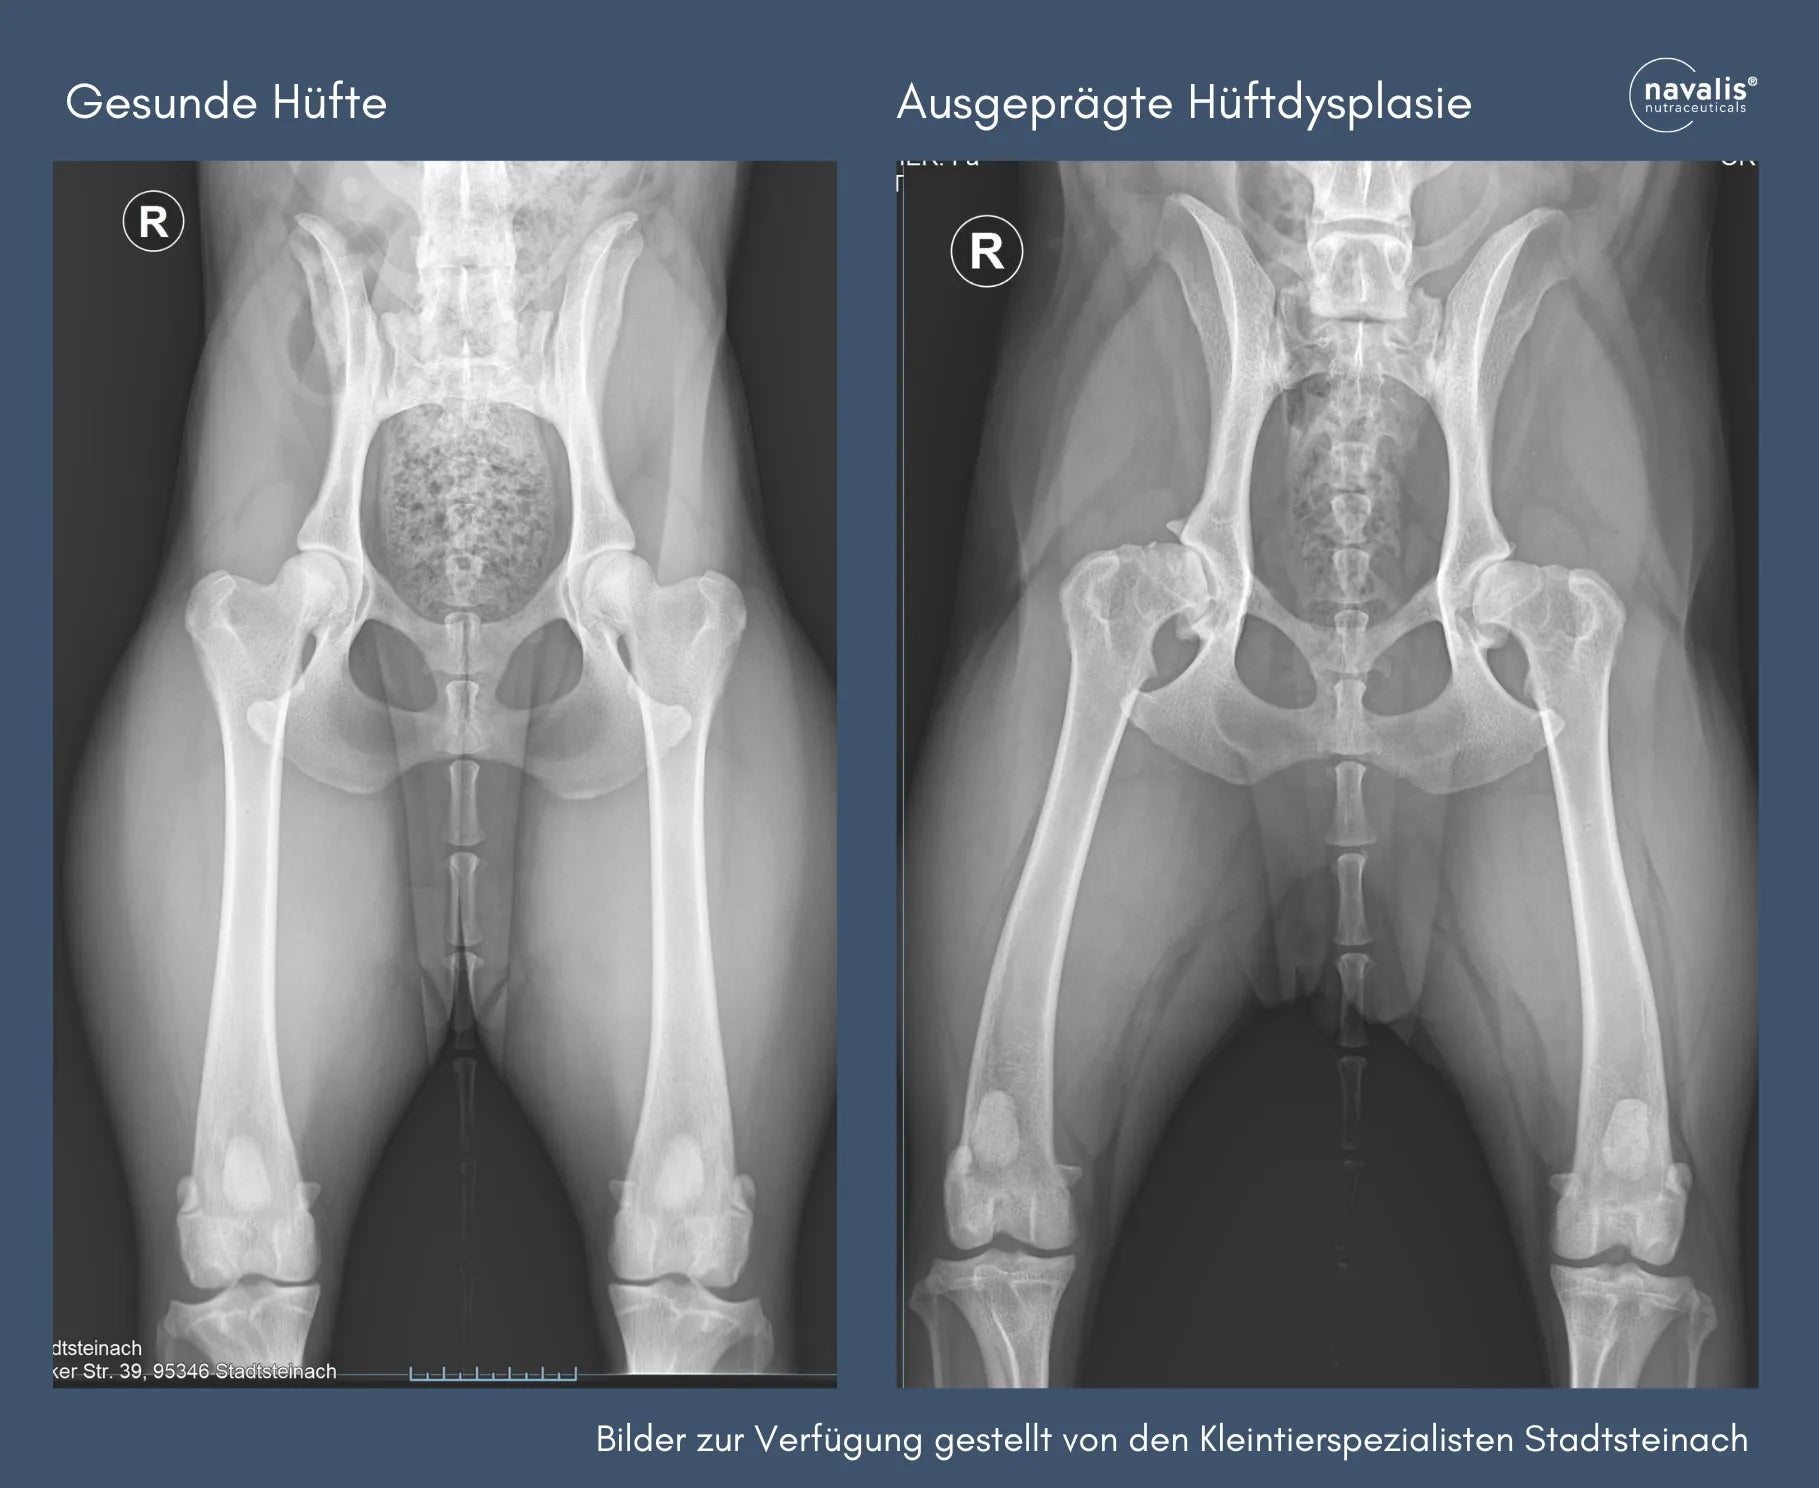

Genetisch bedingten Gelenkproblemen sind u. a. die Hüftgelenksdysplasie (HD), deren Ursache eine Inkongruenz (ein "Nichtzusammenpassen") von Hüftpfanne und Hüftkopf zugrunde liegt. Ellenbogendysplasie gilt als eine erbliche Erkrankung, die besonders bei großen Hunderassen vorkommt, häufig bei Deutschen Schäferhunden, Labradoren und Retrievern.